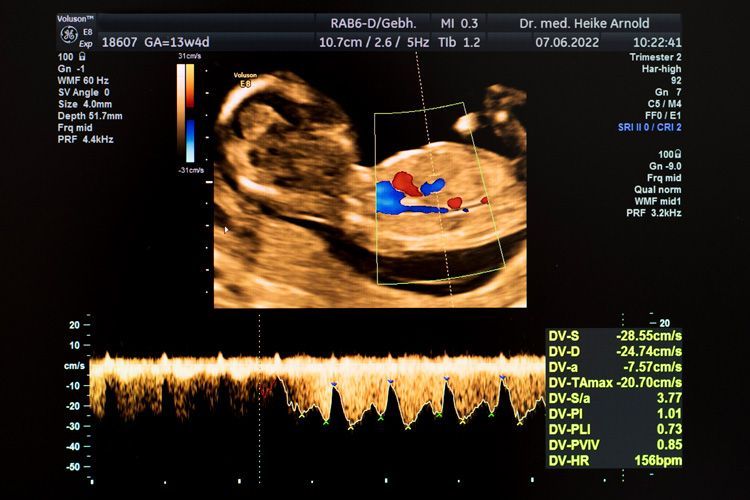

Doppleruntersuchung

schwangeren Gebärmutter kann helfen, das Risiko einer mangelhaften Mutterkuchenfunktion rechtzeitig zu erkennen und gegebenenfalls medikamentös zu behandeln.

Im Schwangerschaftsverlauf kann durch die Durchblutungsmessung (Doppleruntersuchung) von wichtigen, kindlichen Blutgefäßen das Risiko einer Mangelversorgung erkannt werden.